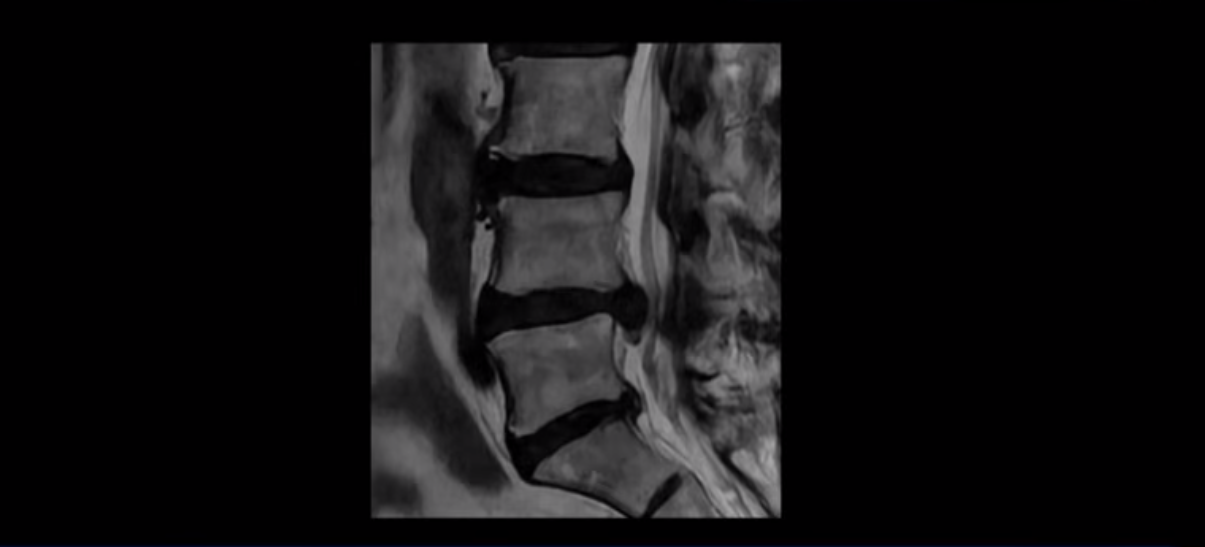

이분 MRI를 먼저 보실까요. 보시다시피 척추 여러 마디가 퇴행되어 있고

4번 5번 마디에는 심한 디스크 파열이 있습니다.

밀려 나온 수핵이 밑으로 흘러내려가 있는데, 이분의 증상은 급성 디스크 증상은 없고 협착증 증상이라서 이 디스크 파열은 오래전에 발생해서 이미 밀려 나온 수핵이 흡수되지 않고 굳어있는 상태로 보입니다.